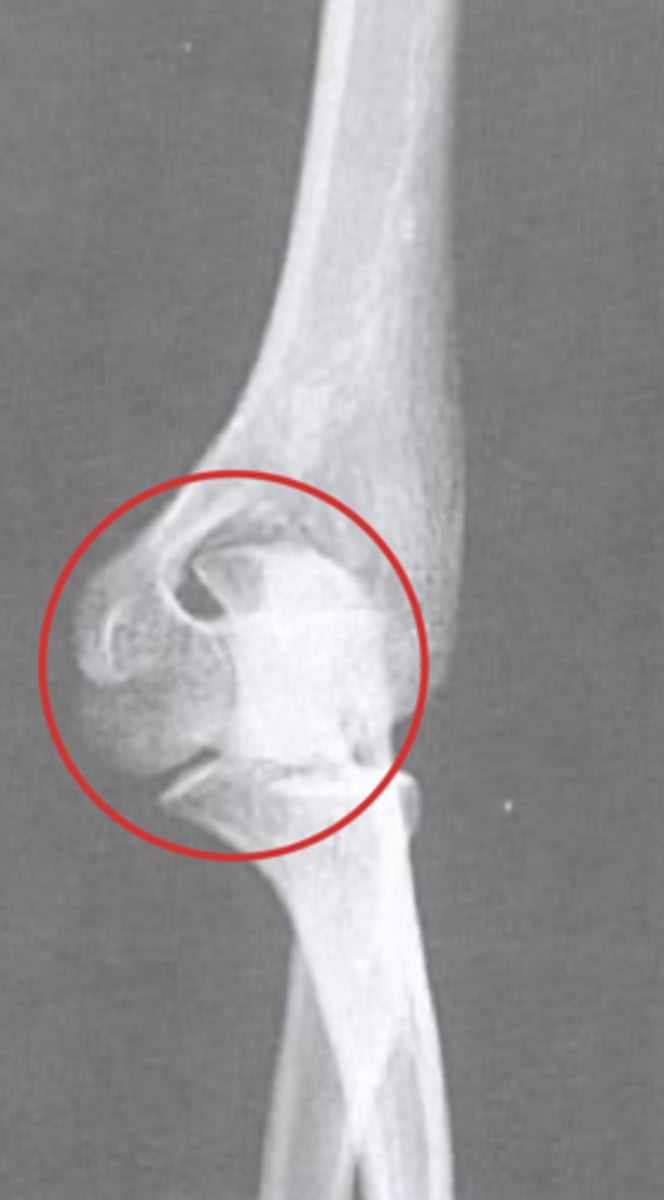

Medial epicondyle avulsion fracture

What is the issue?